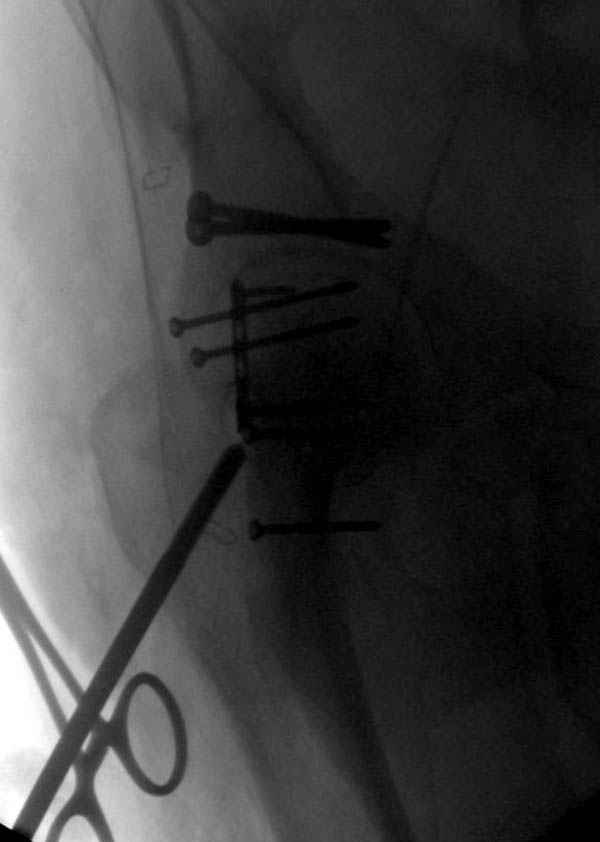

На седьмой день зафиксирован перелом ацетабулума через задний доступ. Перед операцией для профилактики DVT, IVC фильтер, также получает Lovenox.

Латеральное положение облегчает проведение тракции через вертел, за 5 мм стержень за вертел (грузом через тракционное приспособление), на обычном рентгенопрозрачном операционном столе, а для положения на животе, наверное, Judet Table более приемлем, потому что там имеется латеральное тракционное устроиство.

Там множество обычных 2.7 мм шурупов, потом идет фиксация основными пластинами.